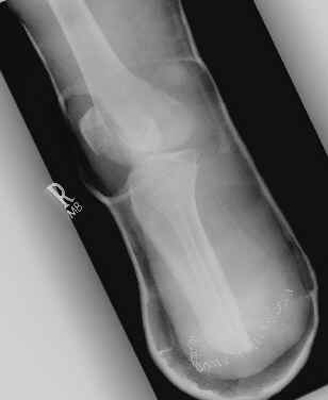

The images shown demonstrates a BKA of acceptable length. The patient is

wearing a prosthesis.